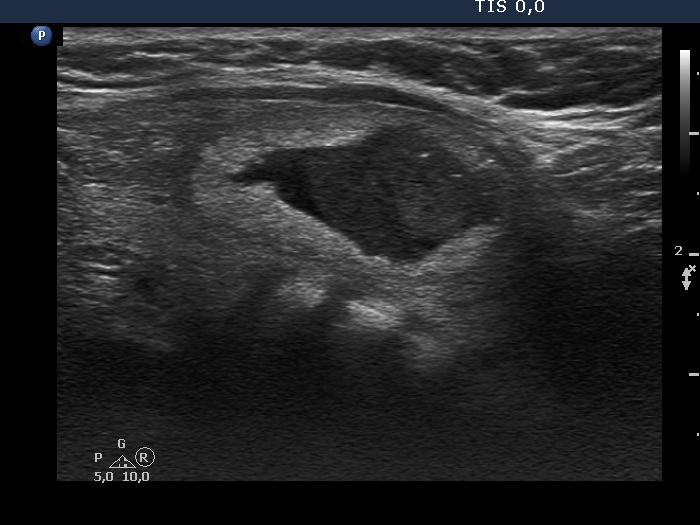

The nodule has several bright and pale granules without a tail and without the synchronous presence of hyperechogenic lines; therefore we have to conclude that these figures are punctate echogenic foci.

Benign cystic degeneration (cytological diagnosis) - case 808